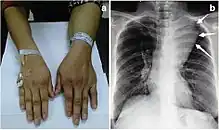

Large mediastinal angiolipoma

Angiolipoma is a subcutaneous nodule with vascular structure, having all other features of a typical lipoma. They are commonly painful.[1]:624[2]